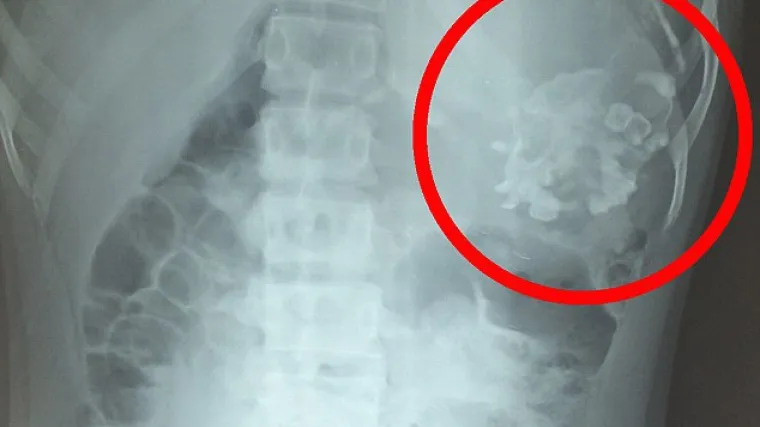

fetus in fetu

ŠOK ŽIVOTA:

Nitko ne bi htio ovako što u želucu

Dvogodišnji dečak nosio svog blizanca u utrobi (VIDEO)